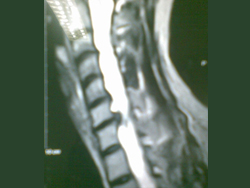

Cervical Spine Surgery in Dehradun, Uttarakhand

Cervical Spine Surgery- Reconstruction